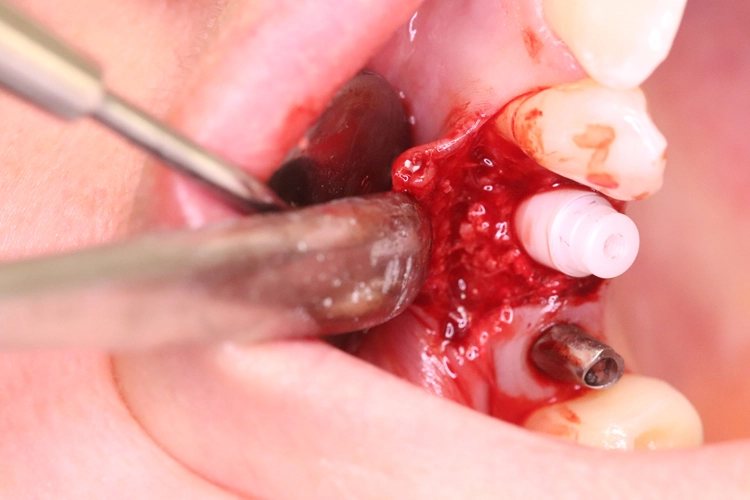

Aufgrund der traumatischen Extraktion des ankylosierten Zahnes, die zu einer Osteotomie wurde (Abb. 3), fehlten die vestibuläre und palatinale Lamelle (Röntgenkontrollbild während der Osteotomie, Wurzelrest noch vorhanden Abb. 4). Dieser Wurzelrest wurde entfernt. Bei dem geringen Restknochenvolumen war eine Sofortimplantation nicht mehr indiziert.

Der Erhalt der Weichgewebsstrukturen und des Kieferkamms wurde durch das Einbringen eines Knochenaufbaumaterials im Sinne einer Socket/Ridge Preservation ohne Membran gewährleistet (Abb. 5). Mesial zum 13 wurde eine resorbierbare Naht (SABAsorb rapid) gesetzt, um die Weichgewebe zu adaptieren. Die Kontrolle des Heilungsverlaufs nach dem Eingriff erfolgte ein Tag später (Abb. 6).